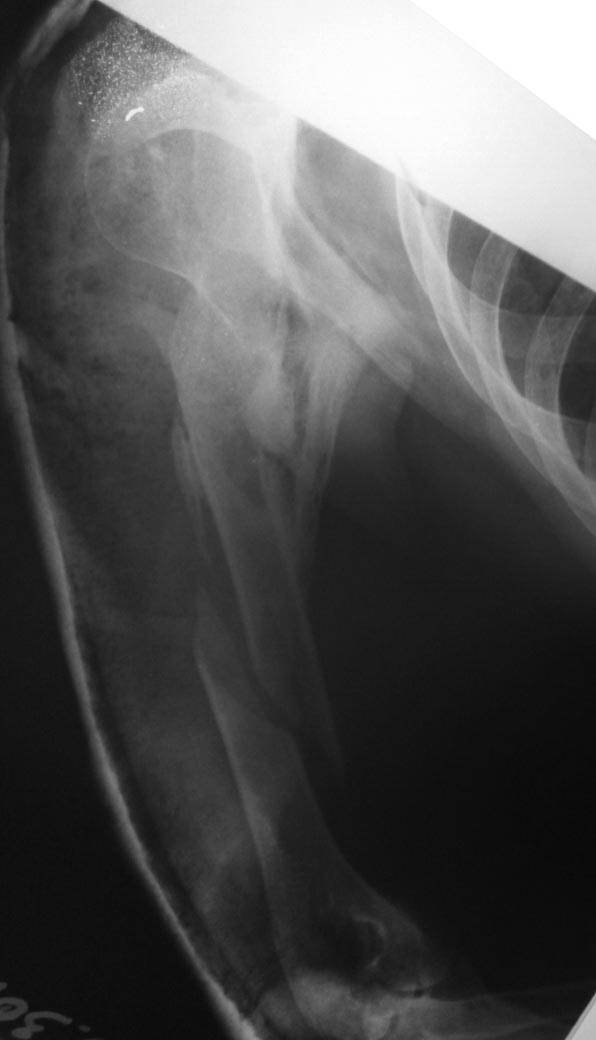

Больной в 2014 году находился на лечении в одной из Московских

клиник.Диагноз:  ТСТ.Перелом черепа Ушиб головного мозга. Диффузное

аксональное повреждение.   Длительное время находился на ИВЛ.

Фрагментарный перелом плеча - консервативное лечение. Перелом голени -

остеосинтез АНФ.

На данный момент больной лежит в кровати. Речь понимает, отвечает

односложно.  Самостоятельно мог поворачиваться в пределах кровати.

Поднимает нижние  конечности , сгибание в коленных суставах и суставах

стоп отсутствуют. При выполнении ЛФК - получен винтообразный перелом

плечевой кости.

У коллег прошу совета: есть мысль попробовать   выполнить

корригирующую остеотомию на уровне в\3 плечевой кости с последующим

остеосинтезом переломов длинным гвоздем. Или выполнить остеосинтез

ретроградным штифтом для дальнейшей возможности корригирующей операции,

Т.к опыта таких операций нет.